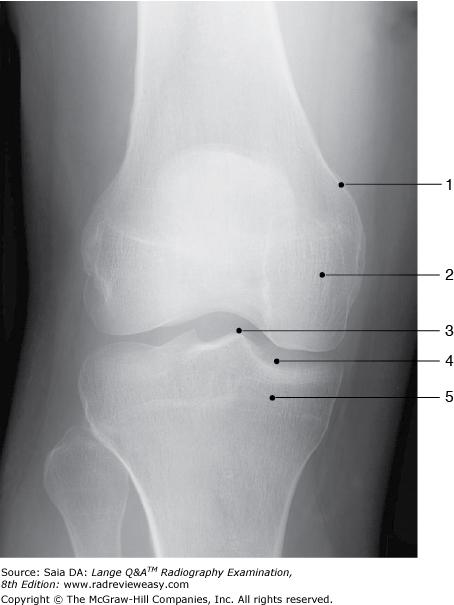

Identify the structure labeled 1 in the AP projection of the knee shown in Figure 2–16.

A Lateral condyle B Lateral epicondyle C Medial condyle D Medial epicondyle

Medial epicondyle